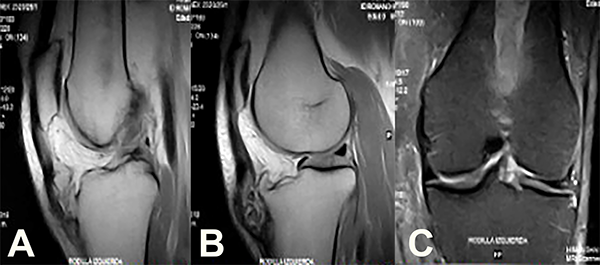

En la resonancia magnética (RM) se pudieron identificar ciertas fibras del TR indemnes, llegando a la inserción distal (fig. 4a) y otras zonas afectadas intrasustancia (fig. 4b). Además, se pudo caracterizar la imagen en el fémur como una displasia fibrosa del fémur distal (fig. 4c).

Figura 4: Cortes sagitales de RM en los que se observan las fibras indemnes del tendón rotuliano (4a) y aquellas comprometidas prácticamente en su totalidad por la tumoración (4b). En el corte coronal (4c) se observa la imagen característica de una displasia fibrosa en fémur distal.